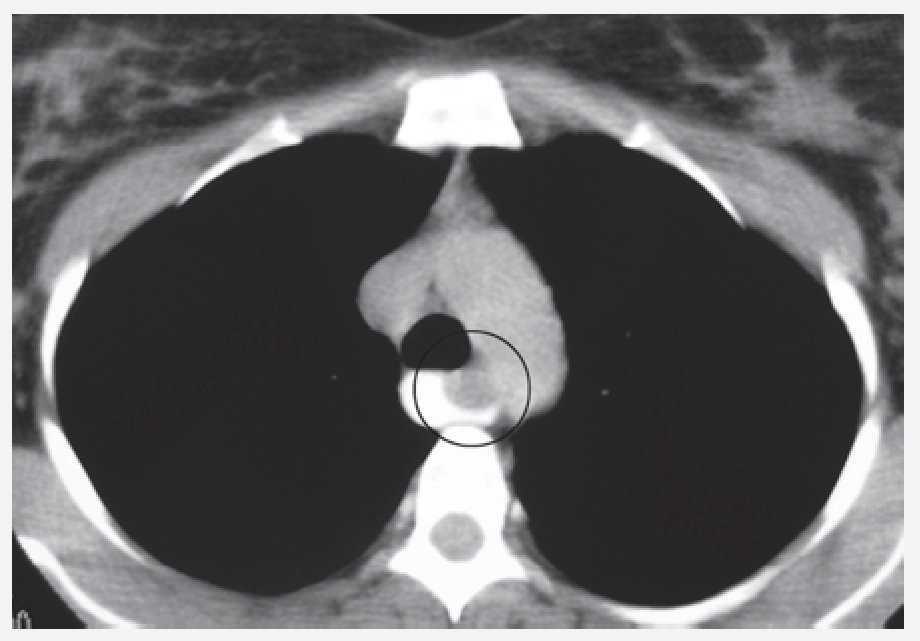

Mujer de 34 años sin antecedentes personales patológicos, quien consulta con historia de 3 meses de evolución de disfagia progresiva. Estudio baritado esofágico reveló compresión extrínseca en tercio medio (Imagen 1). La endoscopia alta mostró una lesión que ocluía 50% de la luz esofágica con mucosa intacta. La tomografía axial computada con contraste esofágico reveló una lesión intramural, no adherida a planos adyacentes a nivel de la pared esofágica lateral derecha en el tercio medio, cercano al cayado aórtico (Imagen 2). A la paciente se le realizó enucleación toracoscópica con abordaje lateral derecho de tumoración esofágica en tercio medio sin complicaciones (Fotos 1 y 2). El informe histopatológico reportó GIST (Gastrointestinal Stromal Tumor) esofágico CD117 (+). Estudio contrastado de control sin estrecheces ni escape. Fue dada de alta al cuarto día posoperatorio.

Imagen 1. Estudio de contraste del esofágico. Evidencia de compresión extrínseca en tercio medio.